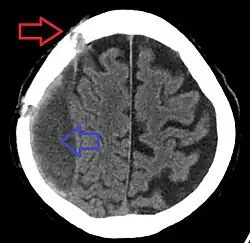

Subdural hematoma as marked by the arrow with significant midline shift

A subdural hematoma demonstrated by CT

Subdural hematomas occur most often around the tops and sides of the frontal and parietal lobes.[3][2] They also occur in the posterior cranial fossa, and near the falx cerebri and tentorium cerebelli.[3] Unlike epidural hematomas, which cannot expand past the sutures of the skull, subdural hematomas can expand along the inside of the skull, creating a concave shape that follows the curve of the brain, stopping only at dural reflections like the tentorium cerebelli and falx cerebri.

On a CT scan, subdural hematomas are classically crescent-shaped, with a concave surface away from the skull. However, they can have a convex appearance, especially in the early stages of bleeding. This may cause difficulty in distinguishing between subdural and epidural hemorrhages. A more reliable indicator of subdural hemorrhage is its involvement of a larger portion of the cerebral hemisphere. Subdural blood can also be seen as a layering density along the tentorium cerebelli. This can be a chronic, stable process, since the feeding system is low-pressure. In such cases, subtle signs of bleeding—such as effacement of sulci or medial displacement of the junction between gray matter and white matter—may be apparent.